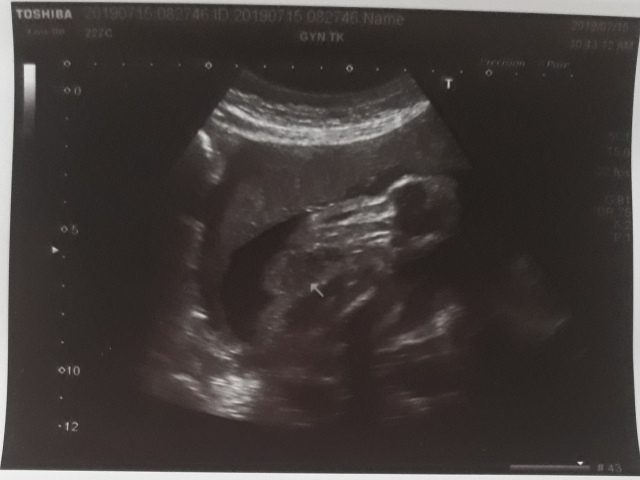

| 仙人掌(2019/07/15)的真心話 星期一 天氣晴 編號19-185 |

29週又3天↓